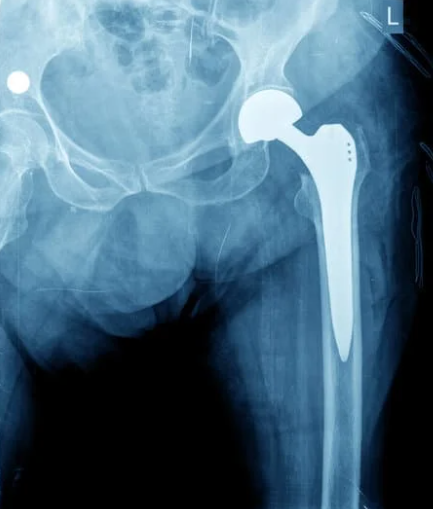

大腿骨頸部骨折は上の二つと同様骨粗しょう症を背景に転倒がきっかけで生じることが多い骨折です。

股関節痛が強く動けない方もいれば、骨折部が噛み込んで安定し歩いて来院する方もいます。

基本的に体重をかけるとズレが大きくなり、骨がつきにくくなるので、よっぽどのことがない限り手術をすることが多いです。

そのため早期診断が大切になります。

診断はレントゲンで行います。

レントゲンはわかりにくい場合もあるため、その時はCTを確認します。

治療は基本的には手術です。

骨を金属の固定具で支え、骨を温存し骨癒合をさせる手術、骨を完全に人工物・金属で置き換える手術、人工股関節に置き換える手術など手術方法は患者さまの背景や骨折のタイプによってえらばれます。